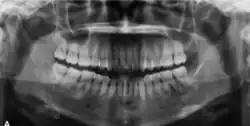

In its early stages, central ossifying fibroma (COF) appears as a small, well-defined radiolucent lesion due to its fibrous tissue content. Differential diagnoses at this stage include periapical pathology, central giant cell granuloma, and ameloblastoma.[22][23] As the lesion matures, it exhibits a mixed radiolucent-radiopaque appearance due to progressive calcification.[22] At this stage, it should be differentiated from other mixed jaw lesions such as fibrous dysplasia, calcifying epithelial odontogenic tumour, adenomatoid odontogenic tumour, and condensing osteitis.[22] In its mature form, COF may appear predominantly radiopaque, resembling lesions like odontomas, osteoblastomas, or osteosarcomas radiographically.

COF typically presents with well-defined, smooth, and often corticated borders. As a central lesion, it originates within the medullary bone and expands concentrically in all directions.[24] With growth, it may cause tooth displacement, root resorption, inferior displacement of the mandibular canal, and loss or alteration of the lamina dura of adjacent teeth.[25]

In conclusion, COF most commonly occurs in the mandible and expands from a central epicenter. Radiographically, it presents as a well-defined mixed-density lesion,[26] and Cone Beam CT (CBCT) plays a crucial role in its accurate diagnosis and assessment.